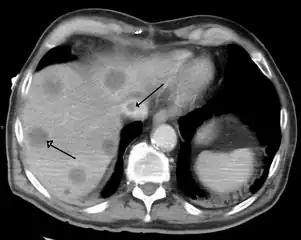

| |

| Budd–Chiari syndrome secondary to cancer, note clot in the inferior vena cava and the metastasis in the liver | |